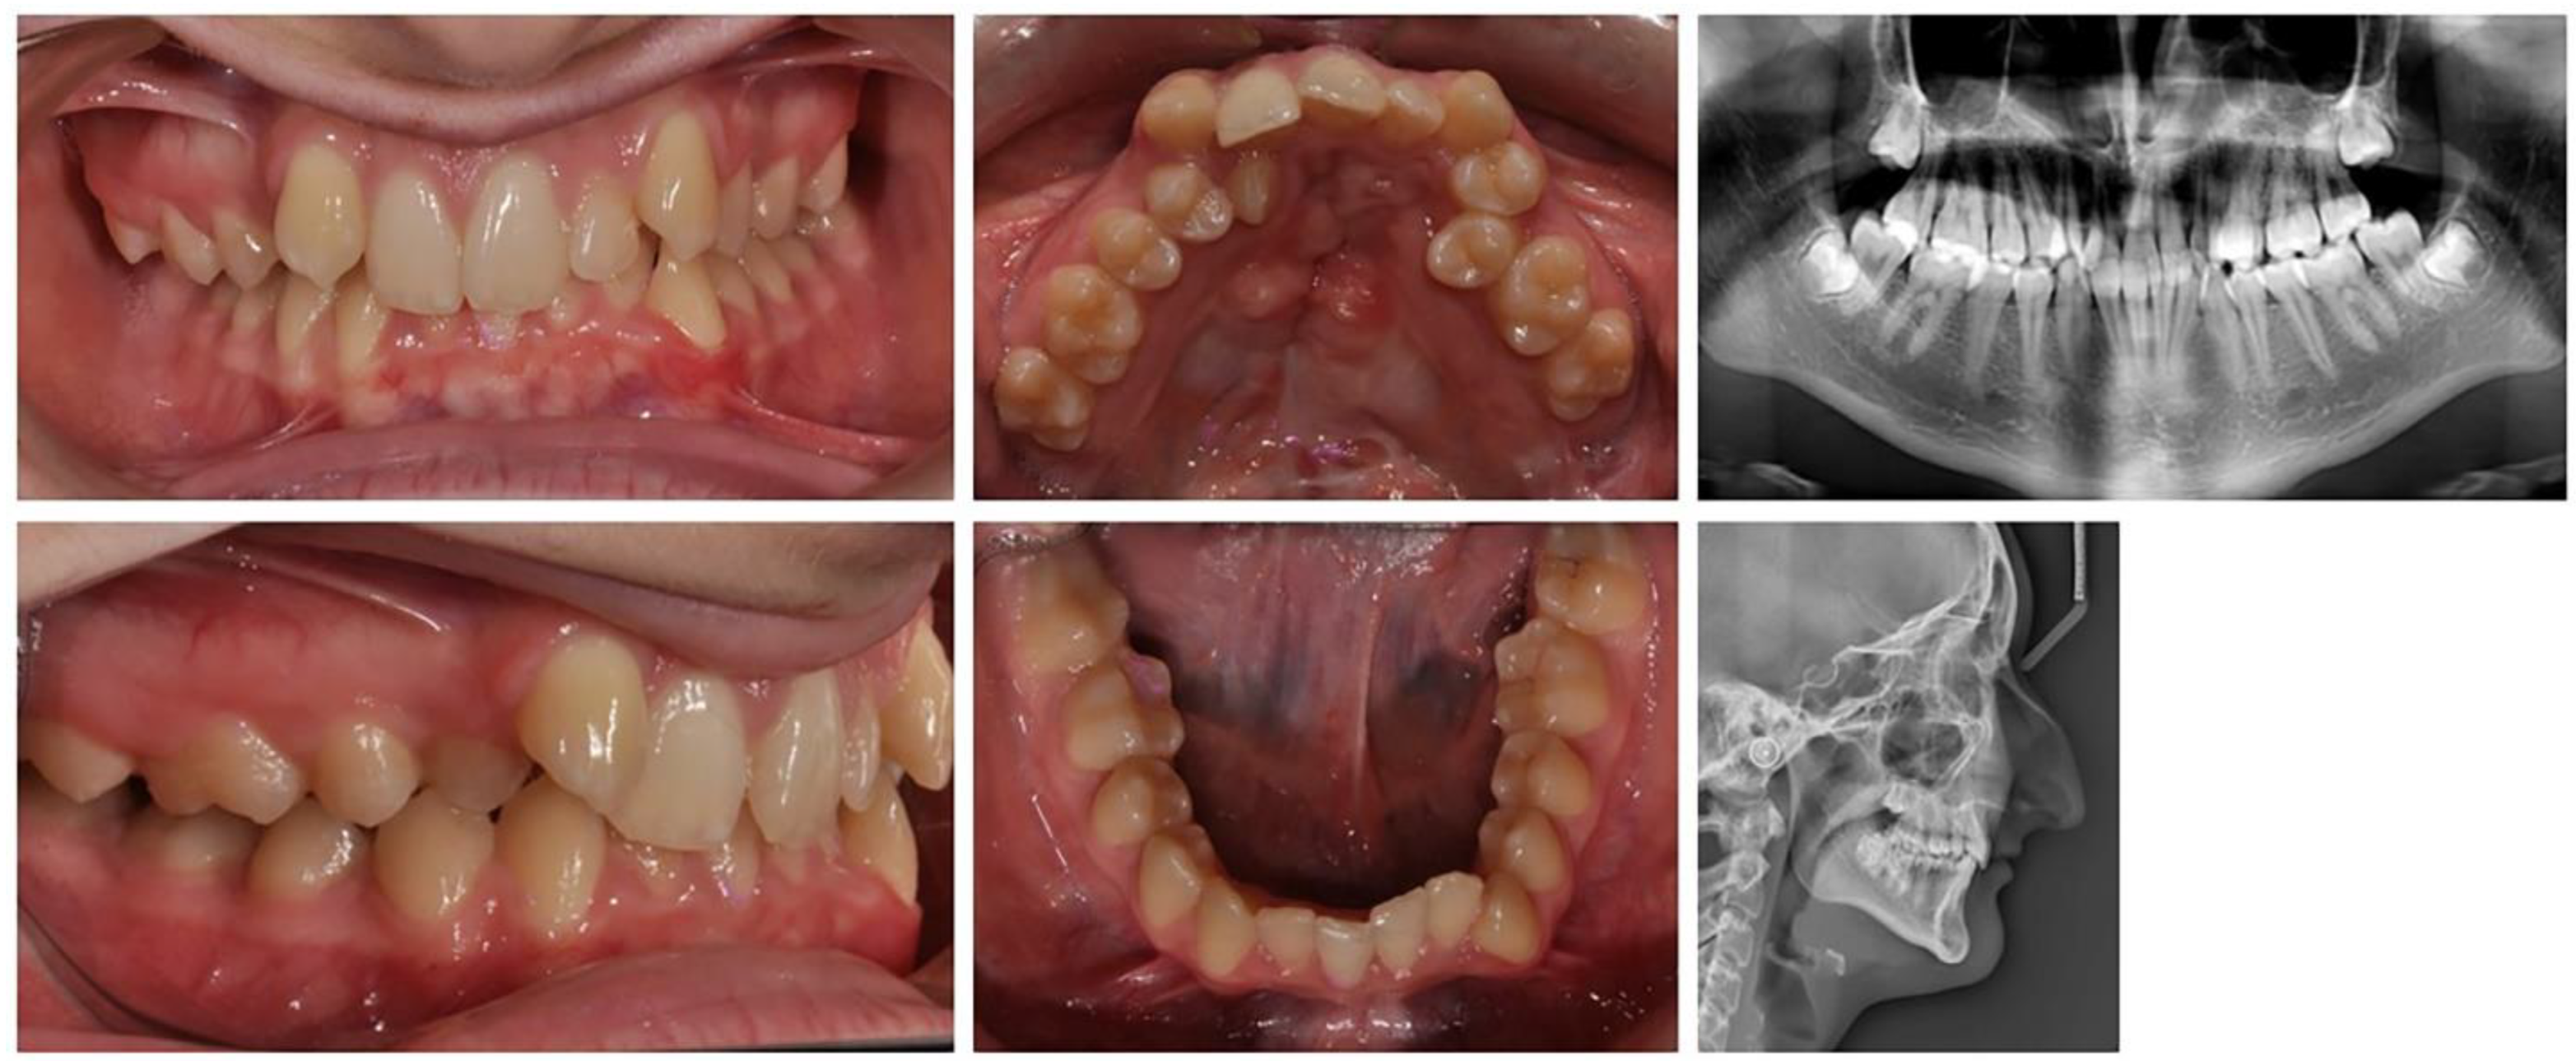

2.2.3. Clinical Case 3–Treatment of Patient with Cleft of the Hard Plate

A 17-year-old female patient with a surgically repaired cleft of the hard palate was included. The patient’s complaint was worsened aesthetics. The upper frontal teeth were retruded and extruded; thus, the bite was deep. During the first clinical examination, a reduced perimeter of the upper dental arch was found, crowding was observed both in the frontal and in the middle segment (in the premolar area) and the shape of the dental arch was trapezoidal (Figure 6).

Figure 6.

Initial status of patient with a surgically repaired cleft of the hard palate.

In orthodontic analysis, the count of medio-distal (MD) diameters of ten teeth from 15 to 25 was MD (15–25) = 63.9 mm. The dental arch perimeter was P (15–25) = 53.83 mm. The discrepancy of MD-P = 10.07 mm was observed (Figure 7). The treatment goal was to provide space in upper dental arch through the extraction of first premolars 14 and 24. The count of first premolar space was almost equal to the discrepancies in perimeter. The upper-right lateral incisor was located on the palate and that resulted in the canine being in contact with the central incisor. The lateral incisor should be included in the dental arch. During the distal movement of the canine, there was a risk of the medialisation of teeth in distal segment and of lost anchorage. Therefore, the use of PDaA was the appropriate decision.

Figure 7.

Digital measurement of discrepancies in the upper jaw.

For the purposes of orthodontic treatment, the extraction of two upper premolars (14 and 25) is required, which will provide a space exactly equal to the crowding size (the sizes of the right lateral and left premolar). It was not desirable to design a biomechanical system which would involve the medial displacement of the distal anchorage teeth, as this occurs with the classic distal displacement of canines and anchorage second premolar and first molar (anchorage type A). In this clinical case, a stable distal anchorage zone was required, which could be provided by mini-orthodontic implants or a rigid transpalatal arch involving all available anchorage teeth (Figure 8). When fabricating this type of digitally planned arch, elements were incorporated into its design to aid in a more bodily movement of the canines, which would reduce the inclination side effects of their movement.

Figure 8.

Transpalatal support arch with extension for the distal movement of maxillary right canine—treatment progress. In blue is the digital design of the PDaA.

The PDaA construction includes first and second molar rings, right second premolar lingual wall, first molar tube and an extended right first molar hook for a higher level of applied canine distalizing force.

The teeth in the upper and lower dental arch were levelled, and the occlusal relationships were normalized. The aesthetics of the frontal segment were restored. From a smile with five frontal upper teeth (13, 11, 21, 12 and 13), a symmetrical smile was achieved with the inclusion of the palatally located upper-right lateral in a normal position. A well-designed metal anchorage system did not allow for the medialization of the abutment teeth. The complete preservation of the perimeter of the upper dental arch was achieved.